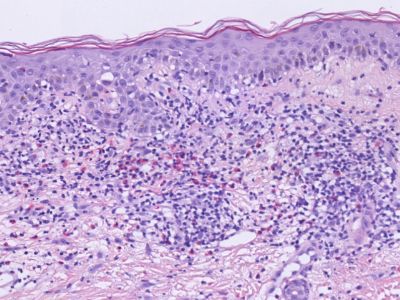

Histologie geneesmiddelreactie Histologie geneesmiddelreactie Histologie geneesmiddelreactie

ingescande coupe (zoom) ingescande coupe (zoom) ingescande coupe (zoom)

Bron hoge resolutie PA-foto's: Kevin Kwee en Afdeling Pathologie MUMC. Klik op de afbeelding om in te zoomen.

De meest voorkomende geneesmiddelenreactie is het maculeuze of maculopapuleuze exantheem, verspreid over het gehele lichaam. Dit is een goed herkenbaar klinisch beeld, hoewel er altijd andere zaken in de DD staan. De diagnose kan worden gesteld op het klinisch beeld en de anamnese (verdacht middel gegeven). Eventueel kan het bevestigd worden met een biopt, als er twijfel is. Een biopt kan geen uitsluitsel geven over welk middel het heeft veroorzaakt. Bij meerdere geneesmiddelen kan het een enorme puzzel zijn. Vaak is er alleen maar achter te komen door middelen te stoppen of te vervangen door een niet verwant middel. Let op de tijdsrelatie: 7-10 dagen voor een type III-reactie, eerder (1-5) dagen als het middel eerder is gegeven. Binnen enkele tot 30 minuten bij een type I-reactie. Enkele dagen tot enkele weken voor een type IV reactie. 1-8 weken voor een TEN. Ook middelen die jarenlang zonder problemen gebruikt zijn, kunnen opeens een toxicodermie veroorzaken (hoewel dat niet vaak voorkomt). Na het staken of vervangen van een middel moet langdurig worden afgewacht. Geneesmiddelenreacties kunnen 1-2 maanden aanhouden en soms nog langer. Het geneesmiddel is vaak al na enkele uren tot dagen volledig uit het lichaam, maar er zijn (bij type IV reacties) klonen van lymfocyten gevormd, gericht tegen een bepaald molecuul, die een reactie veroorzaken in de epidermis. Die lymfocyten hebben een bepaalde levensduur. Soms gaat een reactie helemaal niet over en een enkele keer ontstaat zelfs een maligne T-cel kloon.